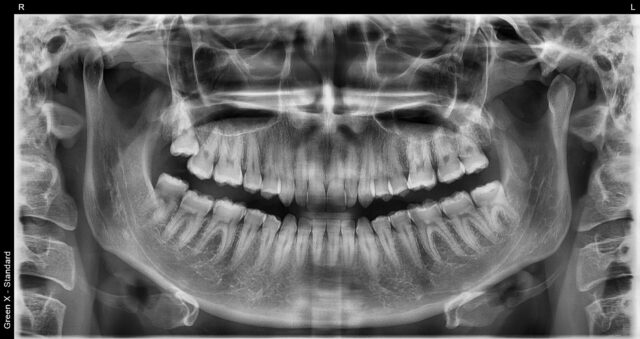

Zdjęcie panoramiczne zębów (OPG, pantomogram) – przegląd całej jamy ustnej

OPG, czyli zdjęcie panoramiczne zębów, pokazuje oba łuki zębowe, stawy skroniowo-żuchwowe oraz zawiązki zębów.

To podstawowe badanie przeglądowe, wykorzystywane w chirurgii (np. przed

usuwaniem ósemek),

ortodoncji, protetyce oraz periodontologii. Jeśli stomatolog zlecił Ci pantomogram, możesz wykonać

rentgen zęba Łódź w formie OPG właśnie u nas.